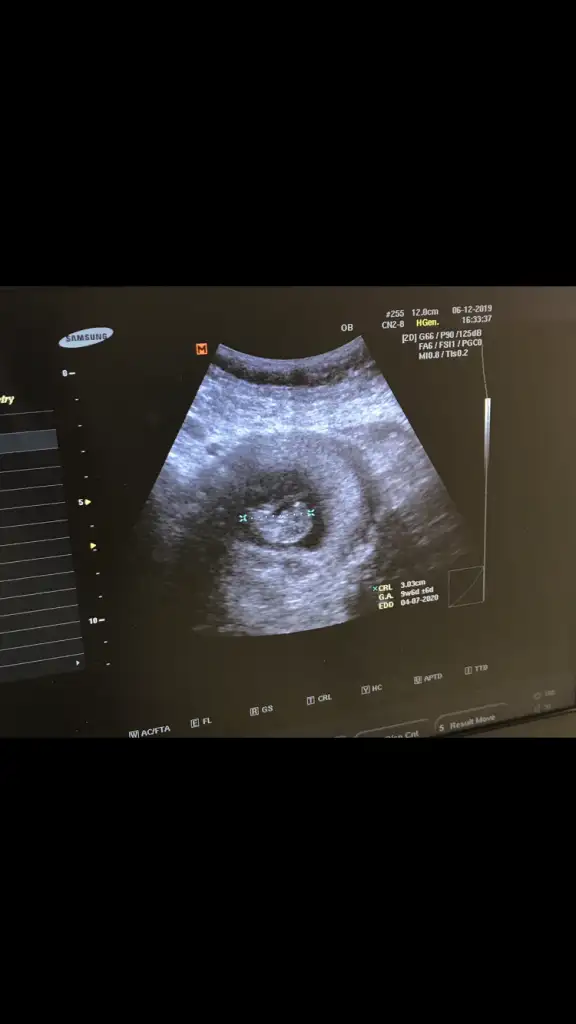

Kız bence 9+6 hafta ya göre

birdahaki kontrol sonucunu size bildireceğimKız bence 9+6 hafta ya göre![]()

birdahaki kontrol sonucunu size bildireceğimteşekkür ederim sevgiler